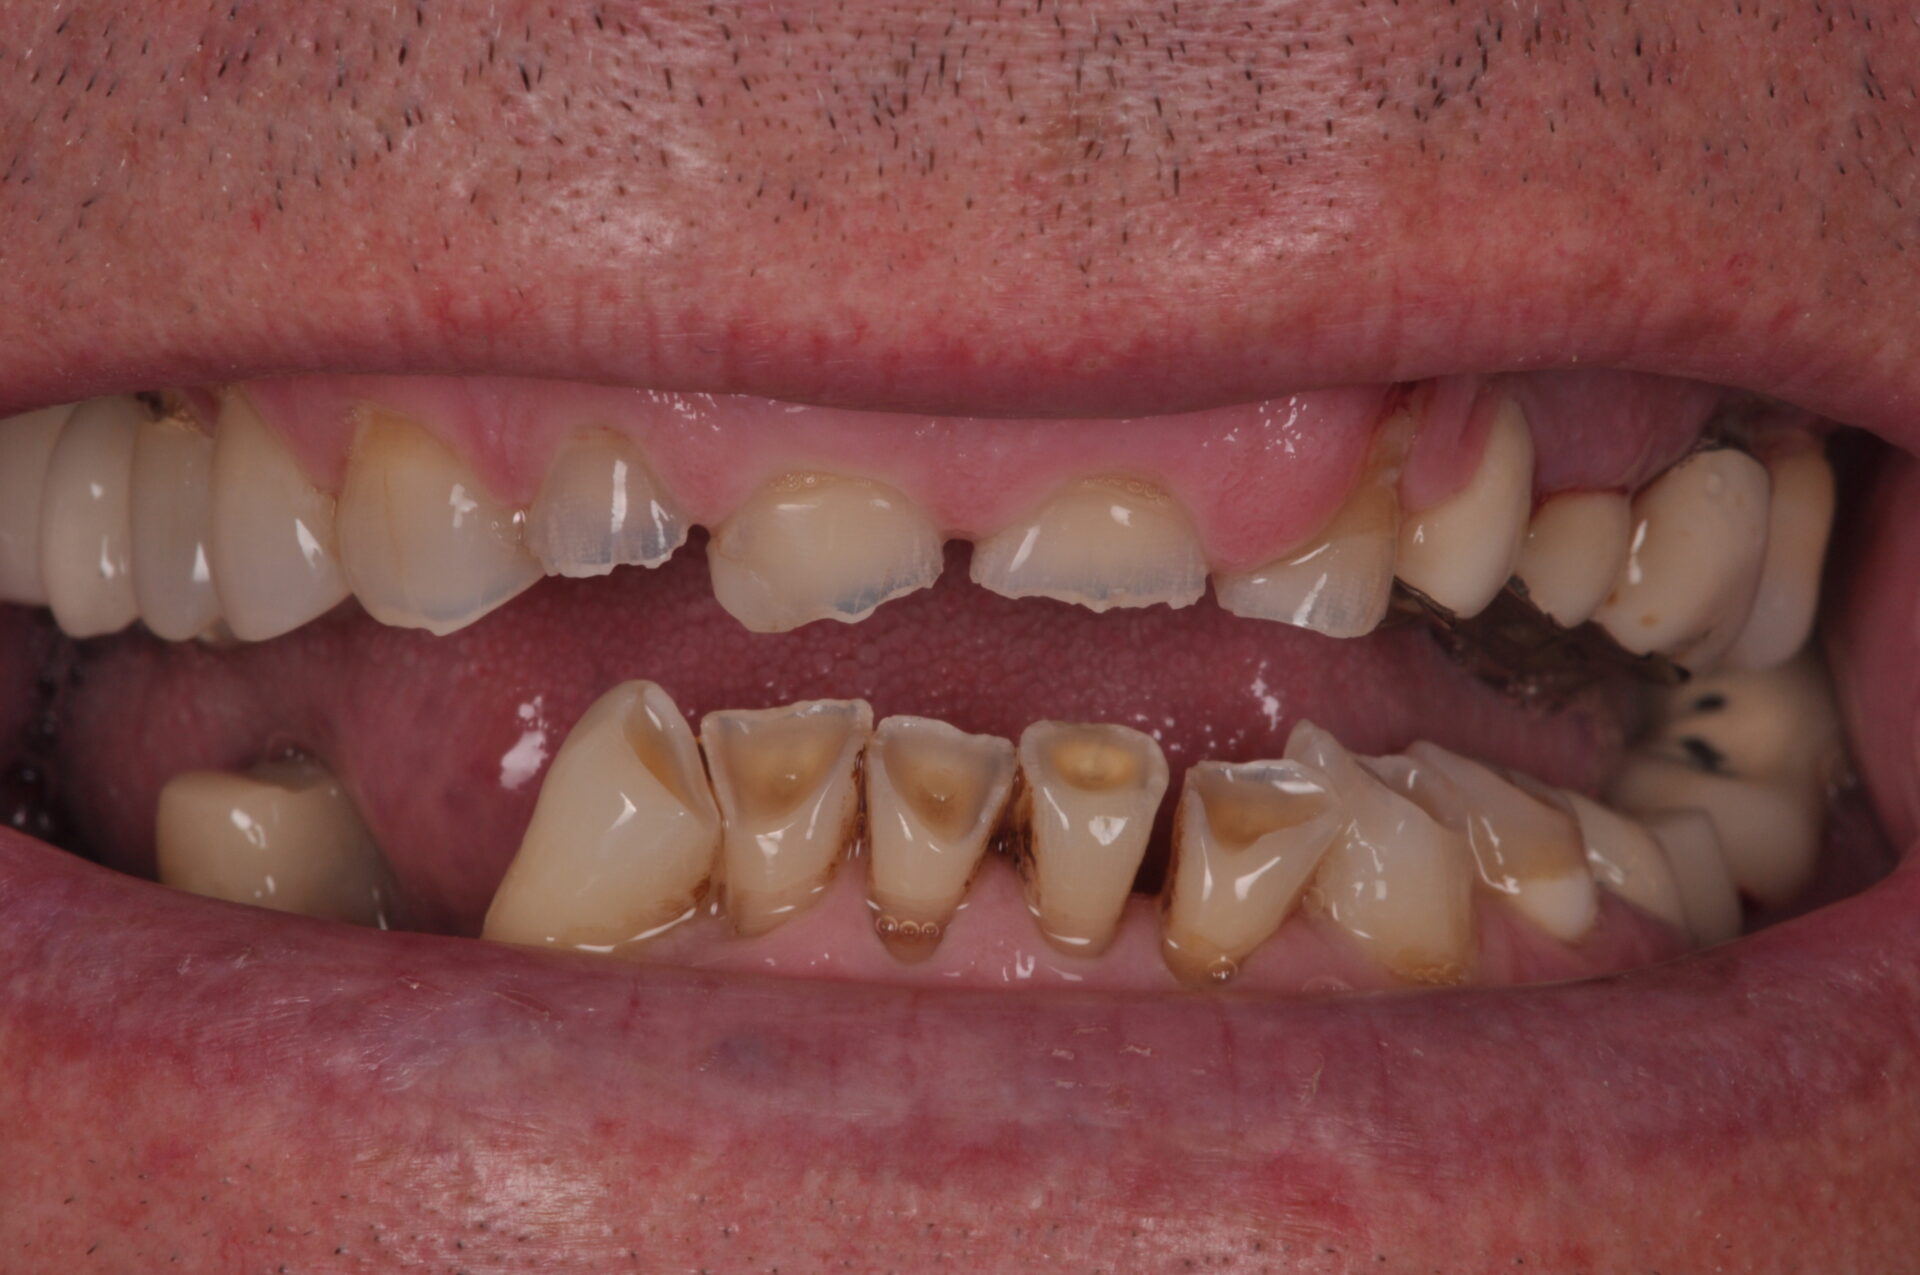

Ejemplo de un caso en paciente con erosiones:

- Antes – Superior

- Antes